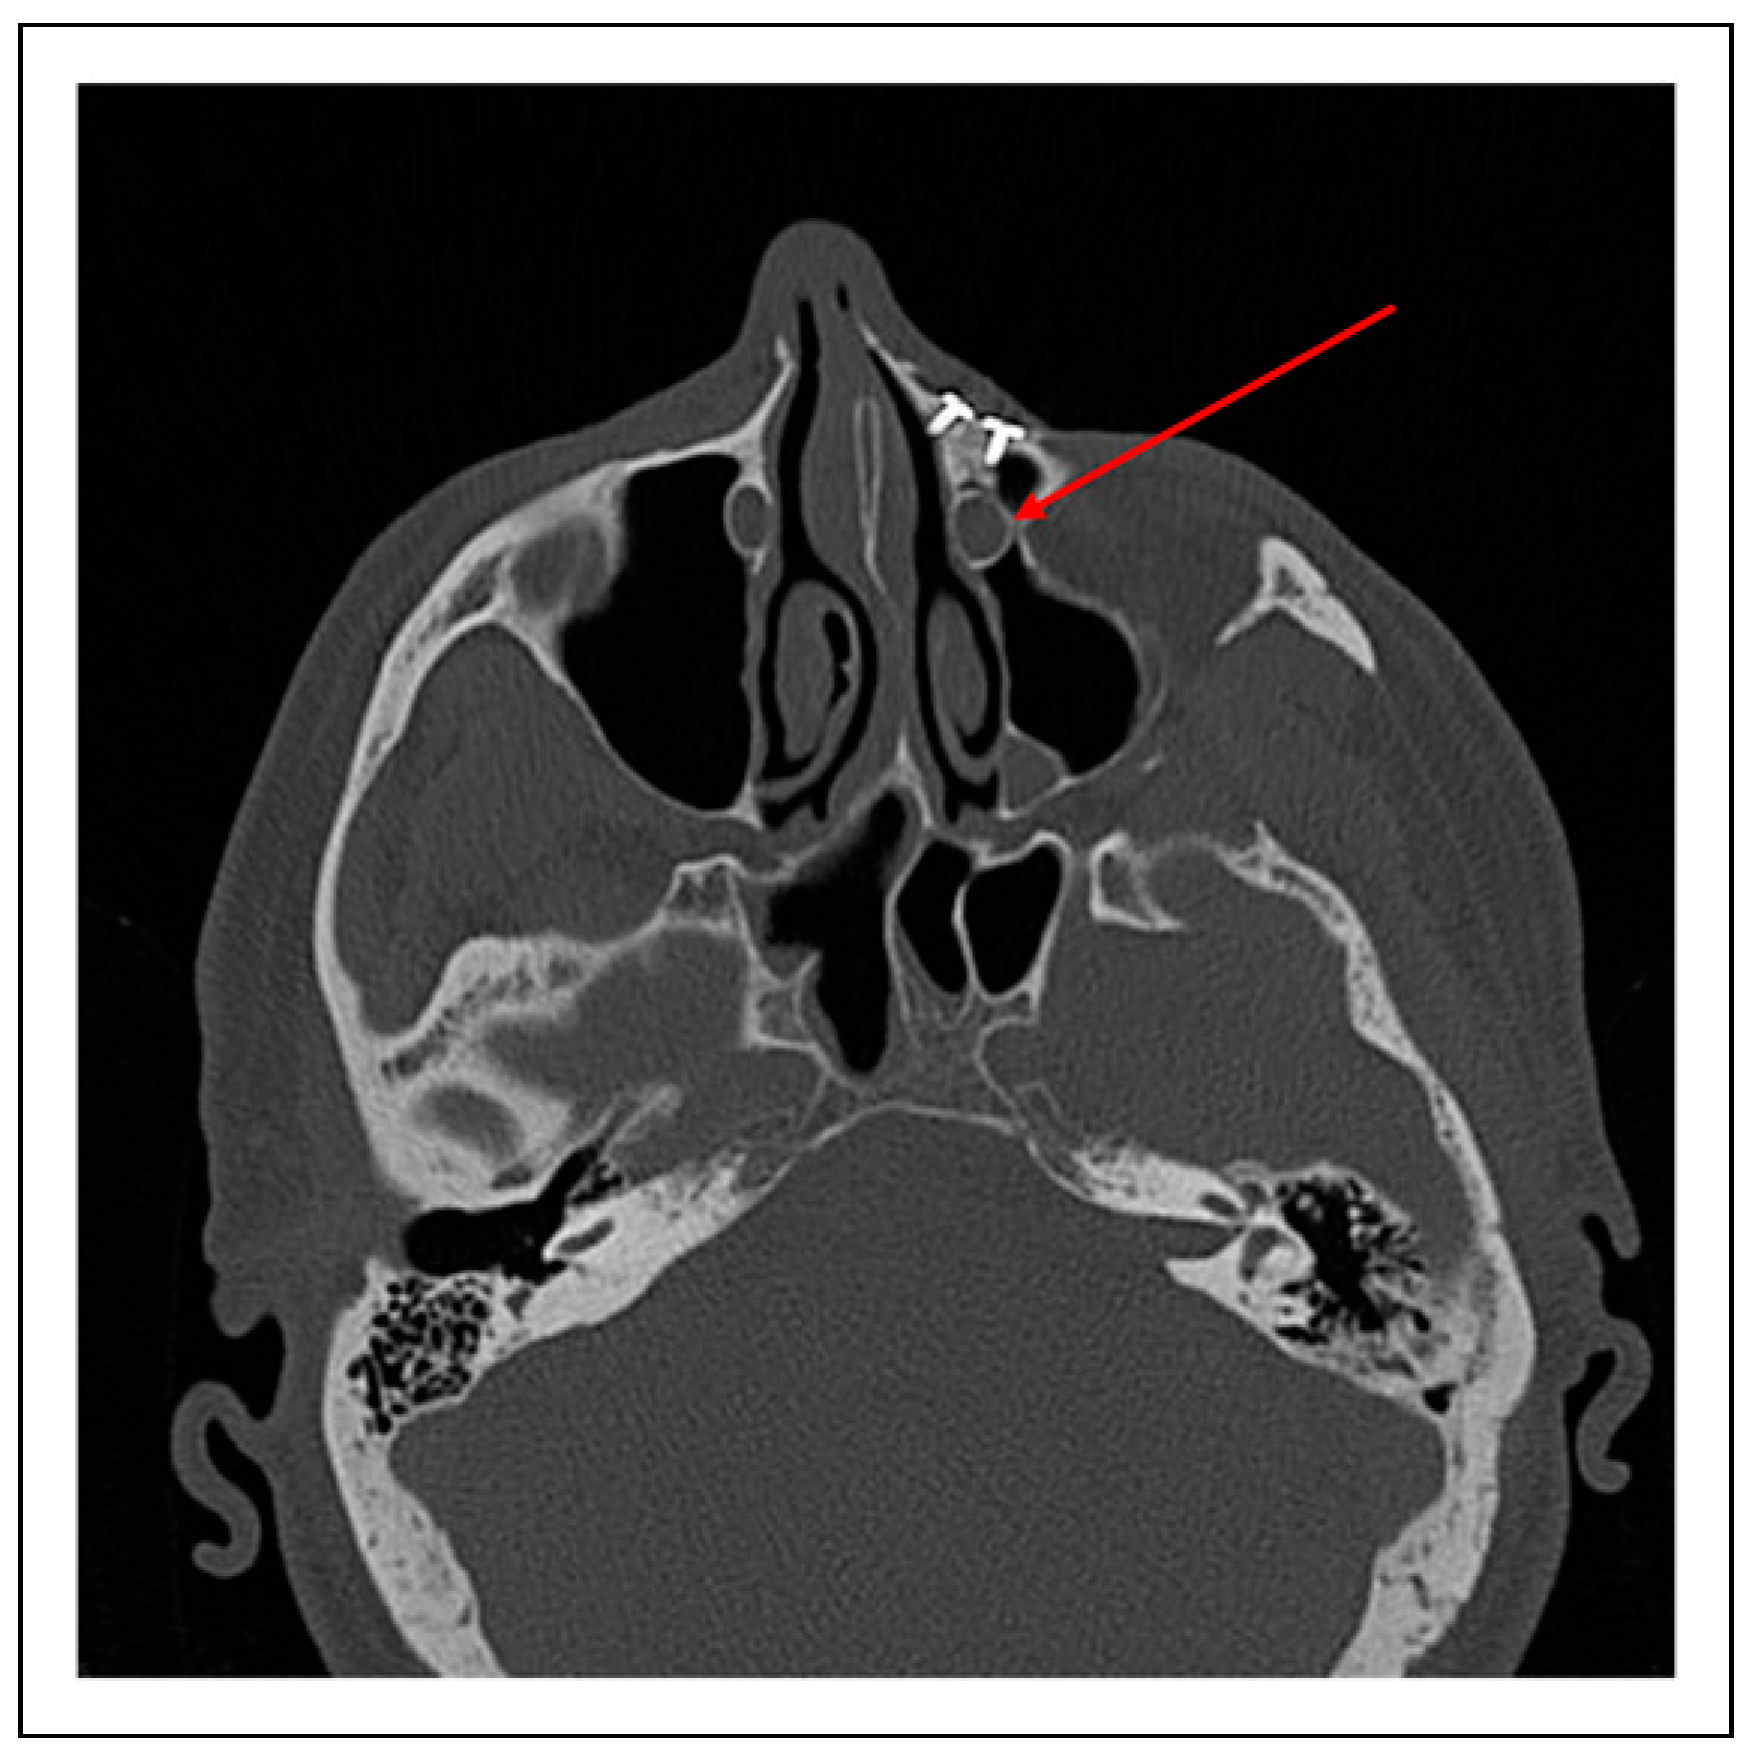

Case 1

Case 2